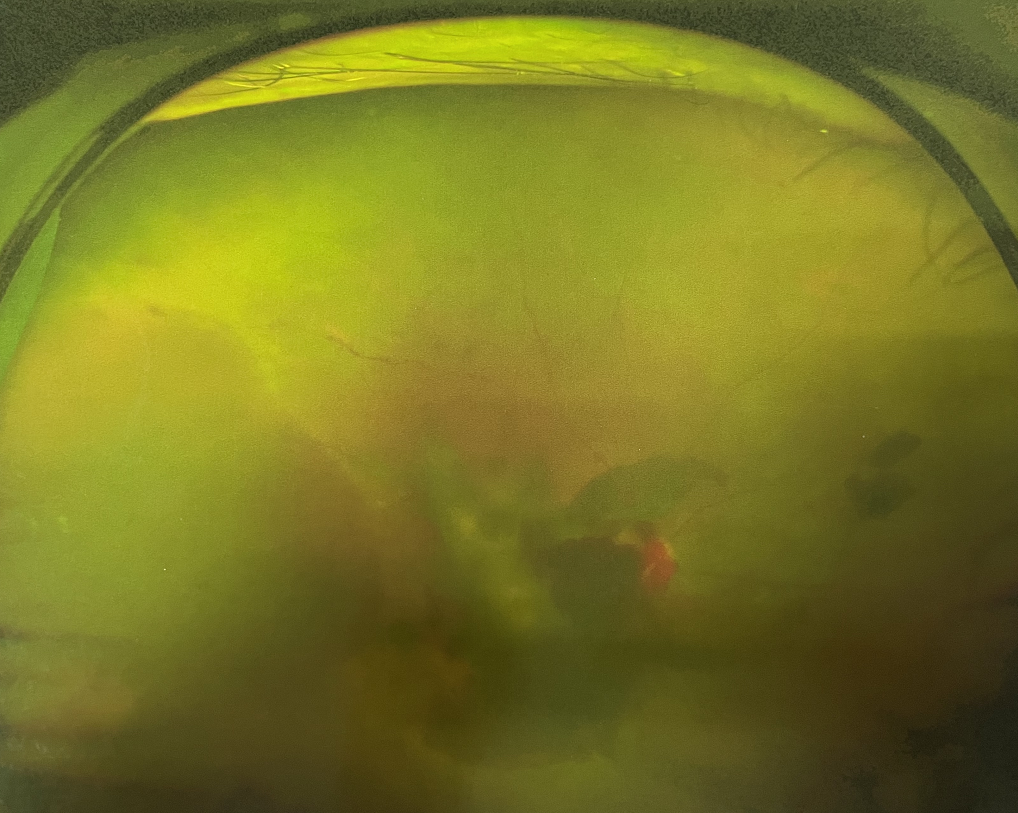

【文章導(dǎo)讀】糖尿病視網(wǎng)膜病變是糖尿病在眼部的主要并發(fā)癥,是我國(guó)四大致盲眼病之一,主要以視網(wǎng)膜血管改變?yōu)椴±硖卣?。眼底多表現(xiàn)為視網(wǎng)膜出血、滲出、新生血管及增殖膜形成,嚴(yán)重威脅患者

糖尿病視網(wǎng)膜病變是糖尿病在眼部的主要并發(fā)癥,是我國(guó)四大致盲眼病之一,主要以視網(wǎng)膜血管改變?yōu)椴±硖卣?。眼底多表現(xiàn)為視網(wǎng)膜出血、滲出、新生血管及增殖膜形成,嚴(yán)重威脅患者的視覺健康。

糖尿病視網(wǎng)膜病變

糖尿病視網(wǎng)膜病變可分為六期:

?、衿冢河形⒀芰龌虿⒂行〕鲅c(diǎn)。

?、蚱冢河悬S白色“硬性滲出”或并有出血斑。

?、笃冢河邪咨?ldquo;軟性滲出”或并有出血斑。

?、羝冢貉鄣子行律芑虿⒂胁Aw積血。

?、跗冢貉鄣子行律芑虿⒂欣w維膜增生。

Ⅵ期:眼底有新生血管或并有纖維膜增生,并發(fā)視網(wǎng)膜脫離。